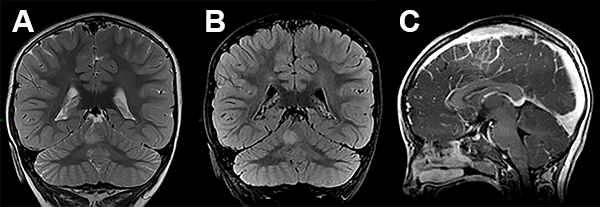

EEG de scalp normal. La RMN de encéfalo mostró una lesión expansiva en la profundidad del hemisferio cerebeloso derecho, en contacto con el pedúnculo cerebeloso superior, con mínimo efecto de masa y sin realce con el contraste (fig. 3).

Figura 3: Caso 2. Imágenes preoperatorias.

A los 29 meses de edad se realizó una exéresis subtotal de la lesión a través de un abordaje suboccipital telovelar (fig. 4). Durante el procedimiento se realizó elecrocorticografía (ECoG), con un electrodo profundo colocado bajo guía ecográfica intraoperatoria que no mostró patrones patológicos. La experiencia en ECoG cerebelosa es escala o nula, por lo tanto se hace muy difícil su interpretación(fig. 5).

Figura 5: Caso 2. Imágenes postoperatorias.